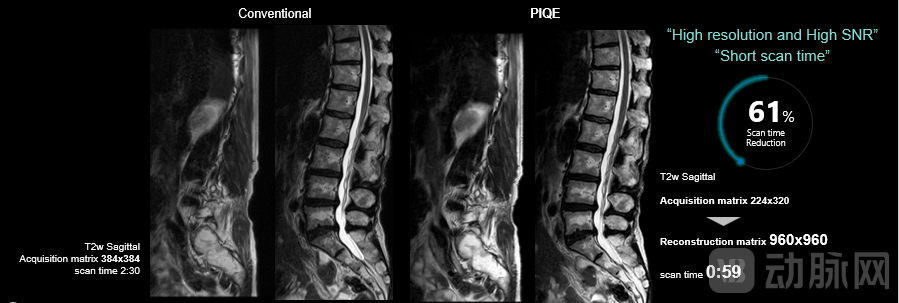

磁共振成像中,信噪比、空间分辨率和扫描时间被称为“制衡三角”,它们之间相互作用,互相制约,共同影响着图像的质量和诊断的准确性。过去,高分辨率图像的获取往往伴随着漫长的扫描时间,这无疑阻碍了图像获取的高效性。高清AI引擎PIQE可以实现增加图像矩阵、减少图像噪声、缩短扫描时间的完美“三重奏”,同时,结合 Real-time 平台,大幅提升数据交换和处理的速度,提升临床诊断效能。

59秒脊柱高分辨率成像

在脊柱成像中,使用PIQE技术,Supreme 在59秒的极速扫描下即可获得960X960矩阵的高分辨率图像,为创伤患者的快速诊治创造了新价值。